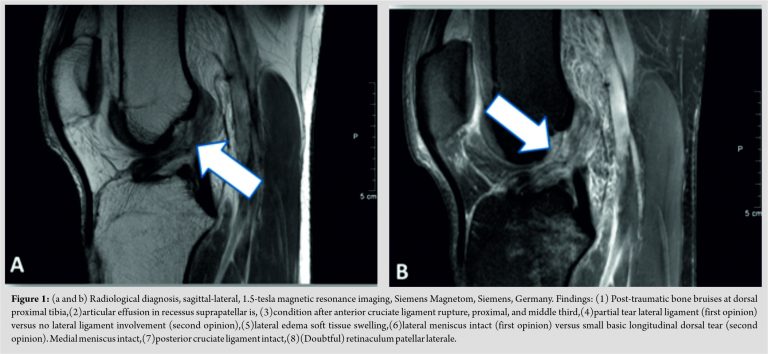

The therapeutic recommendations, based on clinical examination and imaging (Fig. 1) were as follows: The first specialist found no acute surgery indication and recommended to perform a conservative rehabilitation (6 weeks) using a 90° restricted orthosis. A 7-week-follow-up was scheduled to decide on final conservative/reconstructive therapy. The second opinion (and patient’s decision) was immediate surgical reconstruction and subsequent rehabilitation.